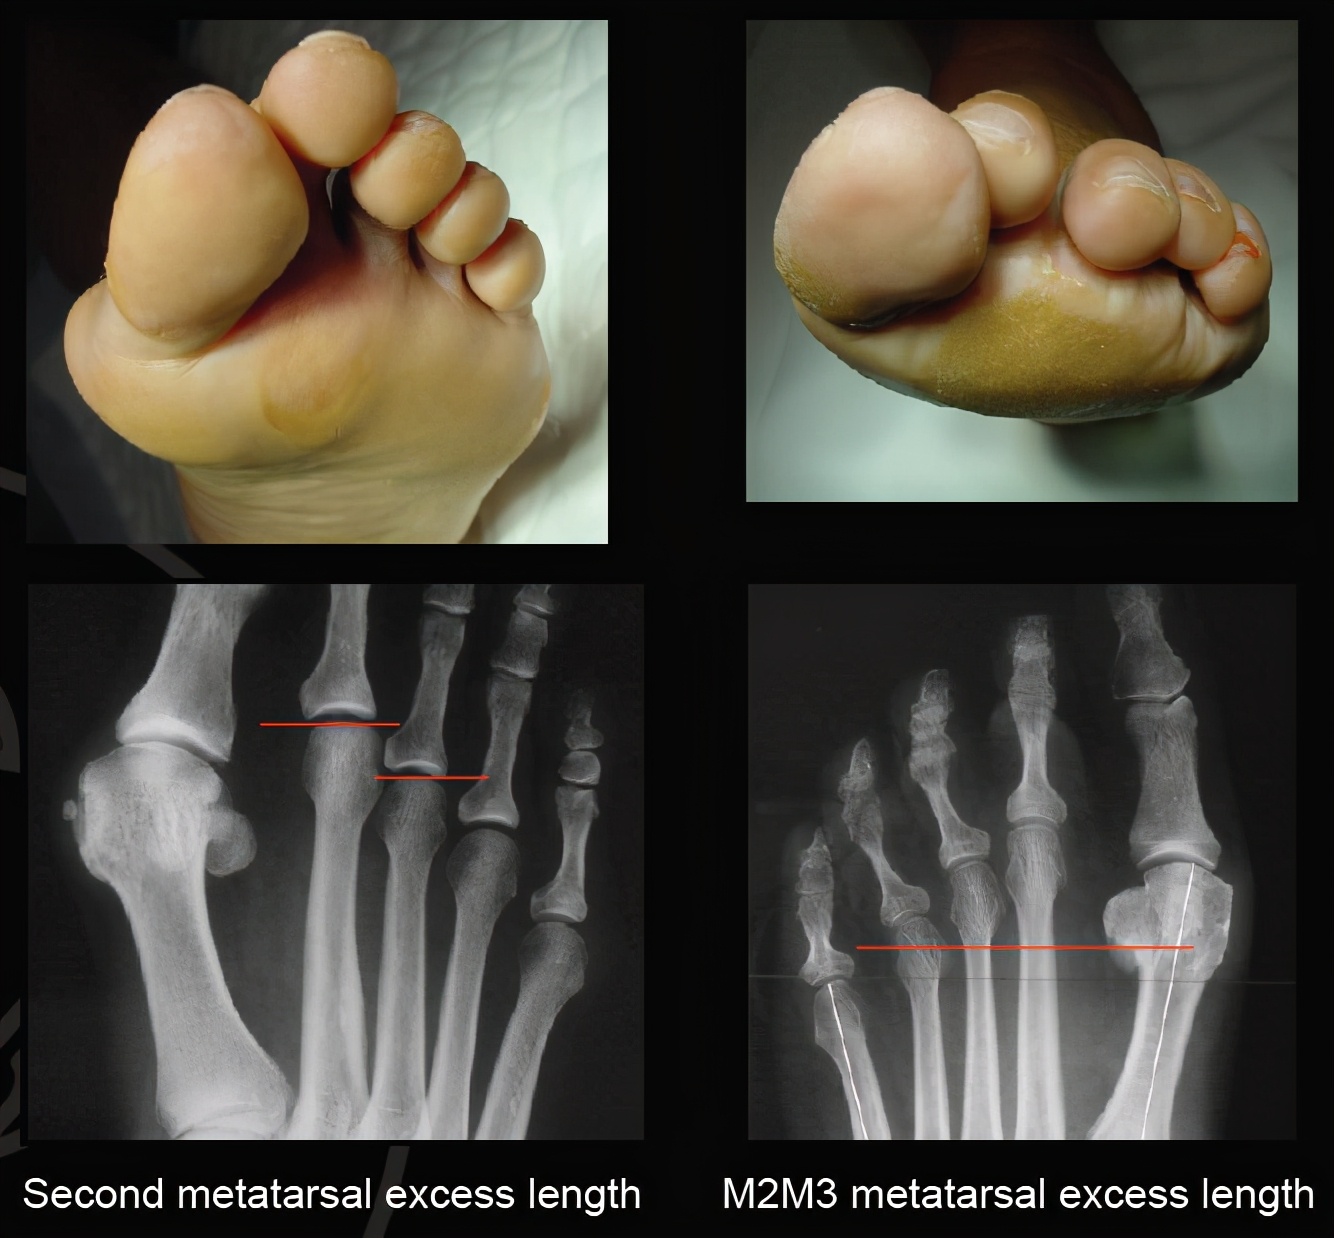

今天因为比较忙,我就不写太多,少写一些内容。大家先看看这个图片:

前足茧子与跖骨的关系

导致前足长茧子主要有几个因素,比方说拇外翻导致前足足横弓塌陷;比方说跖骨长短不协调,上图这个案例就是典型的跖骨长短不协调导致的第二三跖趾关节下方长茧子。

前足的负重主要有第一跖趾关节负重,然后合并前足的足横弓这个特点,就能负责弹跳及日常负重等情况。我们可以看到第一跖骨明显比其余跖骨要粗大,而且第一跖骨下方还有起缓冲作用的籽骨。当第一跖骨过短的时候,或者因为拇外翻导致第一跖骨上抬的时候,原本应该由第一跖骨承受的重力转移到了第二跖趾关节,尤其是图一那种第二跖骨绝对长度较长的朋友们,其第二跖骨会抢着来承受重力,而第二跖趾关节本来设置的时候并不能承受如此重力,第二跖趾关节为了更好承受重力,就只有增加受力面积,这就是第二跖趾关节下方长茧子的原因,讲到这里,你有明白了吗?